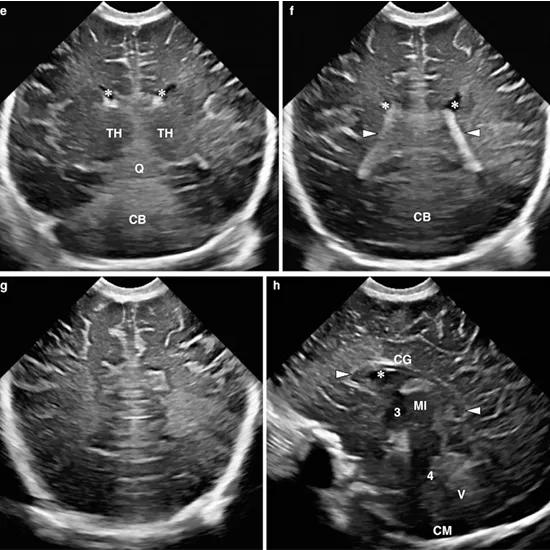

Cranial ultrasound makes images of the brain and its inner fluid chambers by using reflected sound waves (ventricles). These chambers are filled with cerebrospinal fluid. This test is most commonly performed on infants.

A machine sends sound waves into the head during this test, and a computer records the images they create. The black-and-white images depict the inside structures of the brain as well as the fluid that flows within the hollow spaces deep within the brain known as ventricles.